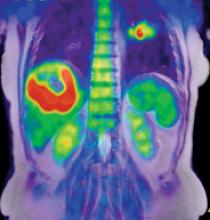

The addition of magnetic resonance (MR) imaging and spectroscopy to positron emission tomography (PET) is more expensive and more technically challenging compared with PET/computed tomography (CT). PET/CT is successful because the inclusion of CT has major advantages: accurate lesion localization, the identification of non-PET avid lesions and effective attenuation correction in a rapid, efficient combined examination. The addition of CT is particularly valuable for lungs and liver, where fluorodeoxyglucose (FDG) PET is limited by spatial resolution and relatively low target-to-background differential biodistribution. Presumably, PET/MR may disclose unique important diagnostic and prognostic information in selected patient groups.